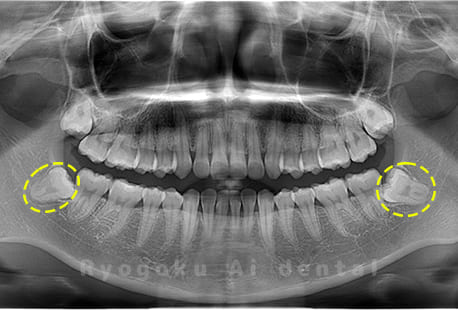

真っ直ぐ生えている親知らず

親知らずが真っ直ぐ生えているタイプです。

このタイプは真っ直ぐ生えていて咬み合わせに問題がなければ、抜歯しないケースもあります。ただし、虫歯になっていたり、痛みがあったり、咬み合わせが悪かったりすると抜歯をおすすめします。